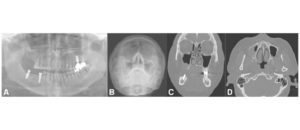

La utilización de la tomografía computarizada de haz cónico (TCHC) en la planificación de implantes dentales ha sido desde sus inicios muy controvertida, la Asociación